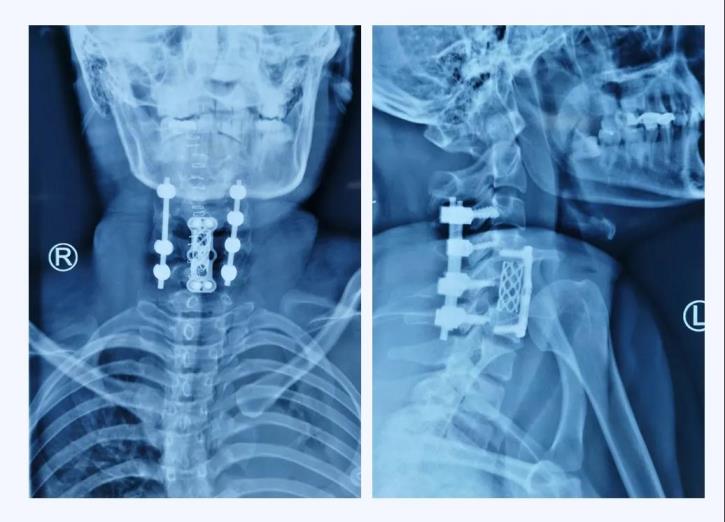

術(shù)后X線

當(dāng)手術(shù)接近尾聲,X線透視機(jī)完美完成術(shù)區(qū)拍攝的一剎那,手術(shù)團(tuán)隊(duì)的所有成員無不發(fā)出由衷的贊嘆,手術(shù)非常成功!頸椎序列完整的恢復(fù)了!

術(shù)后第一天,患者的左上肢已能離床抬起、右上肢肌力也開始恢復(fù)。術(shù)后一周,患者生命體征恢復(fù)正常,肢體功能逐漸恢復(fù)。